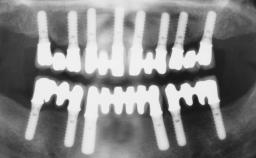

Immediate Loading of Six Implants in the Maxilla and Final Restoration with a Full-Arch Gold/Ceramic FDP Involving the Concept of Tilted Implants

# of Implants 6

Type of Implants One-Piece|Reduced-Diameter

Defining Characteristics Fully edentulous upper jaw to be rehabilitated with four or more implants

Modality Fixed hybrid bridge on 5+ implants